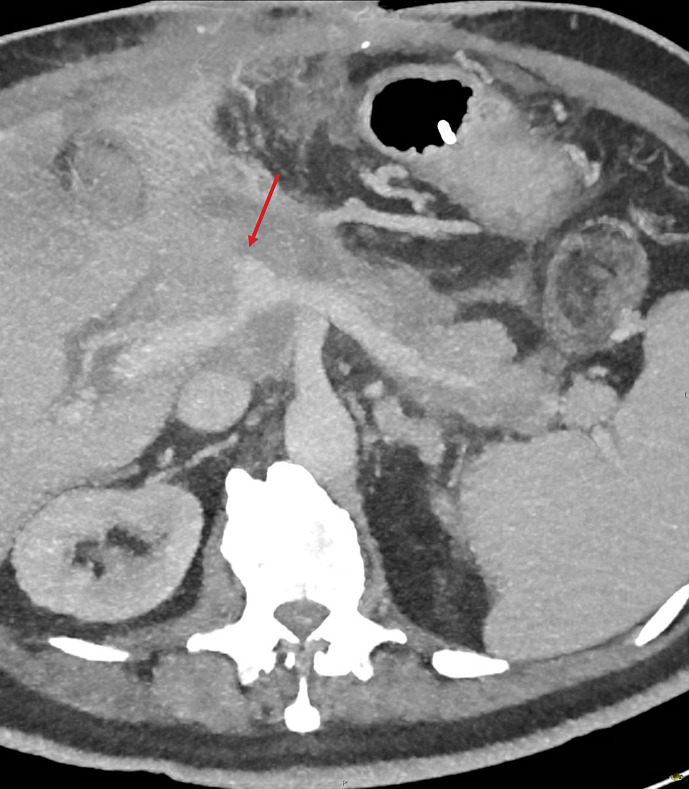

简介:门静脉假性动脉瘤是胰十二指肠切除术后一种罕见但可能危及生命的并发症。我们在此报告这一严重并发症的成功微创治疗:一位 68 岁的男性患者曾在另一家医院接受胰十二指肠切除术和门静脉楔形切除术,因持续胆汁渗漏和间歇性出血来到我科就诊。腹部计算机断层扫描显示,胰空肠造口周围有大量积液,肝总动脉闭塞,门静脉假性动脉瘤。治疗采用了微创方法,包括放置血管内门静脉支架和通过开裂的肝空肠造口进行经皮经肝胆道引流(PTBD)。随后在胰周积液处放置经皮胰尾,以充分引流。放置支架后,抗生素的使用时间共计 6 周。在随后的几周内,PTBD 可以被内化,辫子也可以被移除,之后患者就可以出院了。在门诊就诊时,通过 PTBD 注射造影剂证实没有胆汁渗漏,之后引流管即可拔除:本文介绍了为数不多的已发表的胰十二指肠切除术后门静脉假性动脉瘤病例,并强调了微创血管内支架和 PTBD 置入术在处理这种罕见且可能致命的并发症中的重要作用。

Case presentation: A 68-year-old male patient who had undergone pancreatoduodenectomy with portal vein wedge resection at another facility presented to our department due to persistent bile leakage and intermittent bleeding. Abdominal computed tomography scanning demonstrated a large fluid collection surrounding the pancreatojejunostomy, with an occlusion of the common hepatic artery as well as a portal vein pseudoaneurysm. Treatment was performed by means of a minimally invasive approach, including endovascular portal vein stent placement and percutaneous transhepatic biliary drainage (PTBD) through the dehiscent hepaticojejunostomy. This was followed by the placement of a percutaneous pigtail in the peripancreatic fluid collection for adequate drainage. Antibiotics were administered for a total duration of 6 weeks following stent placement. In the subsequent weeks, the PTBD could be internalized and the pigtail removed, after which patient was discharged. During outpatient visits, a contrast injection through the PTBD confirmed the absence of bile leakage, after which the drain could be removed.